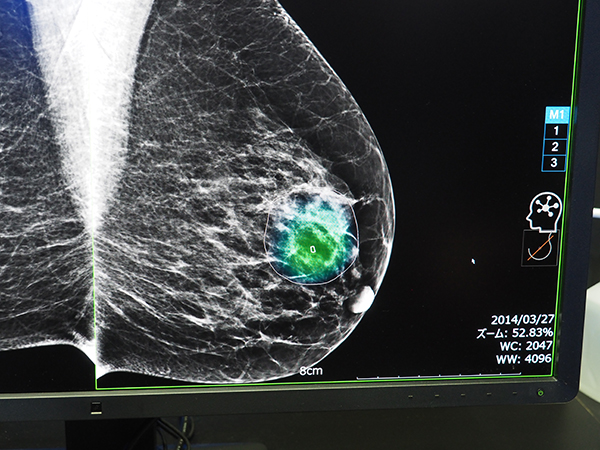

疑わしい病変部領域をヒートマップと輪郭で表示する